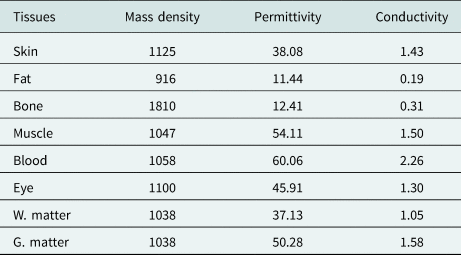

The head model consists of eight tissues: skin, fat, bone, eye, blood vessel, muscle, white matter, and gray matter. The mass density [Reference Kaburcuk and Elsherbeni20], relative permittivity, and conductivity of the head tissues calculated from Debye coefficients in [Reference Kaburcuk and Elsherbeni20] and [Reference Eleiwa and Elsherbeni38] for 2.4 and 5.8 GHz are tabulated in Tables 1 and 2. Figure 3 shows the human-head model's x–y, x–z, and y–z cross sections.

Table 1. Mass density, relative permittivity, and conductivity of the head tissues for 2.4 GHz

Table 2. Relative permittivity and conductivity of the head tissues for 5.8 GHz